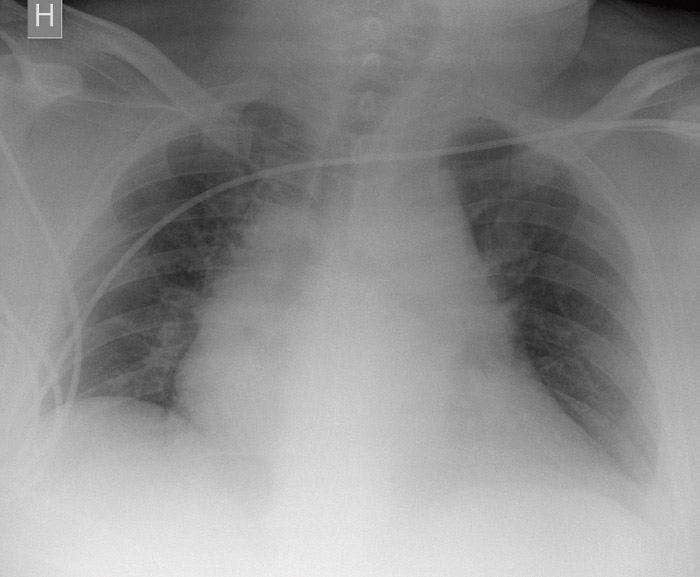

Flere diagnoser ble vurdert. Pasienten oppfylte tre av kriteriene for systemisk inflammatorisk respons-syndrom (SIRS) (puls > 90/min, temperatur < 36 °C, respirasjonsfrekvens > 20/min), og sepsis kunne ikke utelukkes. Cerebral iskemi ble vurdert, hovedsakelig grunnet uro og uklarhet, så vel som lungeemboli. Det ble gitt intravenøs væske og oksygen på maske, men pasienten tolererte ikke masken og ble tiltakende urolig. Arteriell blodgass viste pH 7,29 (7,350 – 7,450), pCO₂ 3,8 kPa (4,67 – 6,00 kPa), pO₂ 11,5 kPa (10,67 – 13,33 kPa), laktat 10,4 mmol/l (0,4 – 2,2 mmol/l) og Hb 12,6 g/100 ml (11,5 – 17,4 g/100 ml). EKG viste sinustakykardi uten iskemitegn. Pasienten var palpasjonsøm supraumbilikalt og myk i buken, men det hørtes ingen tarmlyder. Gastrokirurg så til pasienten og innkalte radiolog for ultralydundersøkelse av typen «focused assessment with sonography for trauma» (FAST). Undersøkelsen viste ingen åpenbare patologiske tegn, heller ingen perikardvæske. Røntgen thorax viste ikke hemo- eller pneumothorax, men ga mistanke om breddeforøket mediastinum (fig 1). Selv om pasienten var ustabil, ble det rekvirert CT thorax.